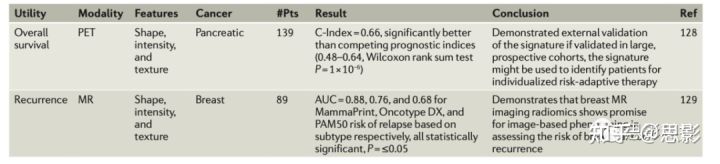

虚拟活检

在癌症患者中,肿瘤的不同部位具有不同的分子特征;这种差异会随着时间的推移而改变。由于不可能在多个时间点对每个肿瘤的每个部分进行活检,因此无法使用活检样本实现肿瘤的最佳表征(图4)。

图4,影像基因组学分析可以揭示成像表型和基因表达模式之间的关系。

这种关系可以包括单个基因的表达,以及总结特定基因亚群表达的度量。